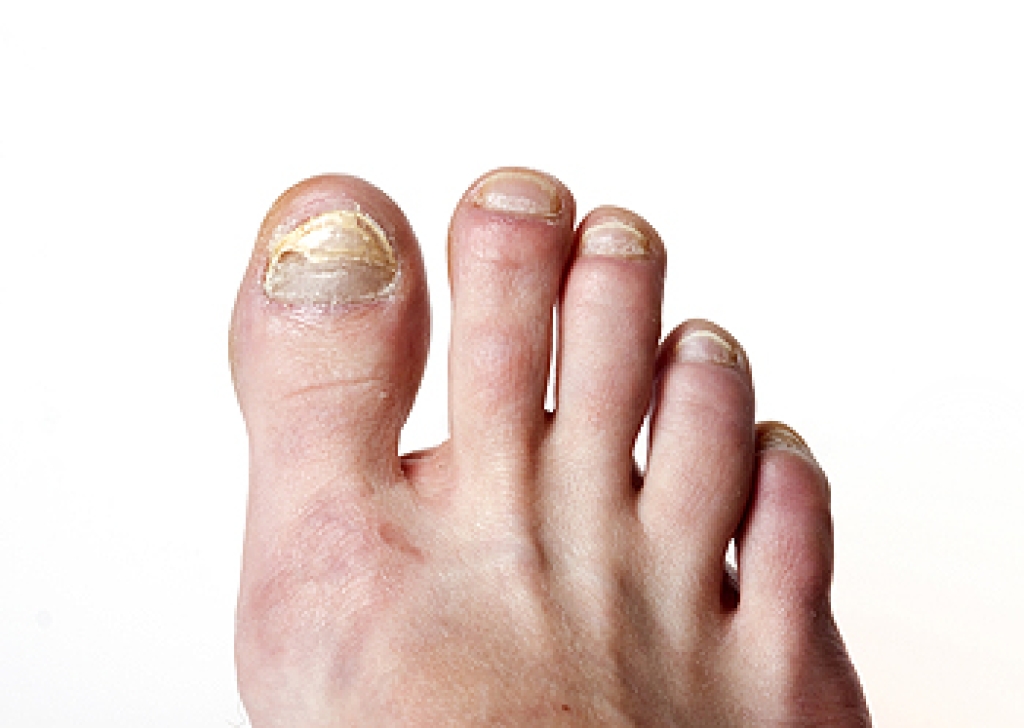

Believe it or not, many illnesses are often initially detected by podiatrists. Our feet can hint at a variety of issues that are occurring throughout the rest of our bodies. For example, problems with blood circulation can cause the feet to change color or feel cold. Simple toenail discoloration can indicate diseases such as diabetes, heart disease, and lung disease. A podiatrist can also tell if toenail discoloration is actually a bacterial or fungal infection. Various kidney diseases can be shown in the feet through ankle swelling or toenail discoloration. Therefore, when experiencing unknown symptoms in the feet, it is important that you consult with a podiatrist to make sure that these symptoms are not indicating a more serious, underlying condition.